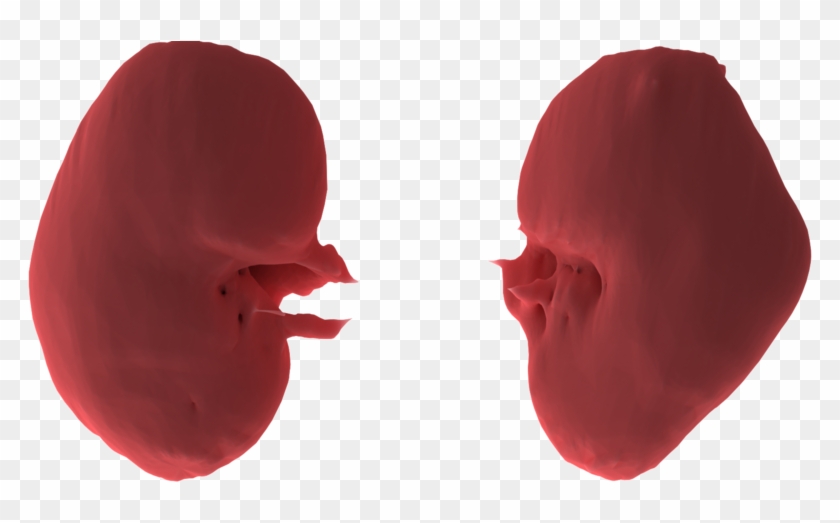

- Name Load In 3d Viewer Uploaded By Anonymous - Illustration Clipart